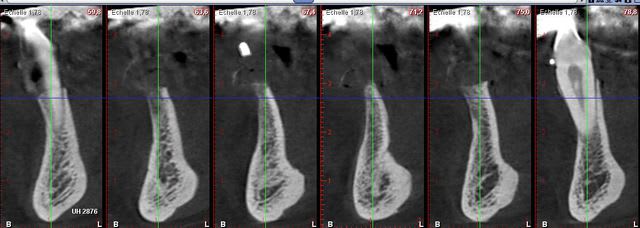

ca ne me semble pas si fin que ça... je régulariserai le sommet de la crete pour retrouver un peu d'épaisseur et je prévois de quoi faire une ROG pour le tiers cervical de l'implant

Je suis d'accord, l'os est précieux. Ici, l'écrêtage est minime, surtout pour la zone de la coupe 71. Il faut avoir tout de même un minimum d'épaisseur osseuse au niveau cervical. Le risque sinon est de voir apparaitre des spires quand la cicatrisation sera vraiment terminée.

Dans un cas comme celui ci, il est possible de "manipuler" la crête (1 mm est suffisant pour la partie crêstale) et avec un implant positionné en sous crêstale (- 1mm), je ne pense pas qu'il y ai des risques de spires découvertes ensuite.

Bien sur travail à la lame n° 15 et pas de violence (pas de piezzo, ni fraise).